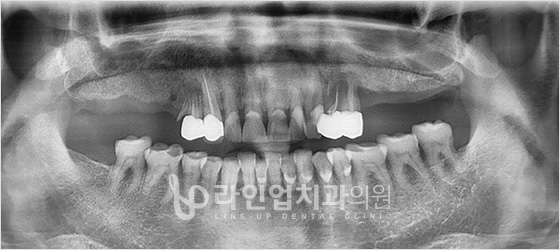

Before

After

Имплантация верхних моляров